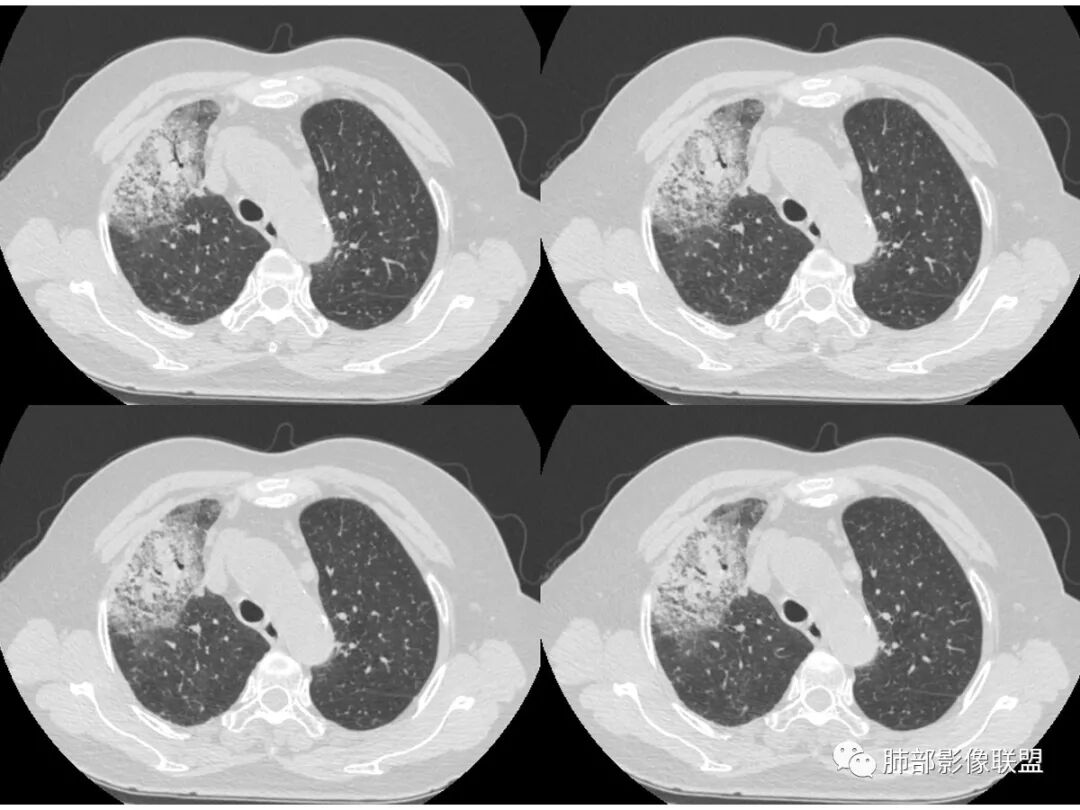

右肺上叶大片状阴影,内见僵硬的支气管,部分支气管轻度扩张,内见一空洞和液平,病灶边缘可见磨玻璃影,首先考虑恶性病变,粘液性腺癌伴感染可能。

老年女性,慢性病史,白色痰液,量多,病灶起于胸膜下,实性加磨玻璃,磨玻璃边缘偏轻,跨叶生长,病灶内可见枯树枝,考虑肺炎型肺癌。

老年女性,右肺上叶大片实变及磨玻璃密度影,磨玻璃边缘清晰,内可见小叶间隔增厚,内可见空洞,似可见分隔,叶间裂局部膨隆,纵膈窗,没有增强,枯树枝不明显,肺炎型肺癌可能,鉴别大叶性肺炎,结核?

胸CT:右肺上叶实变内可见支气管充气征,近端支气管狭窄,远端扩张,周围可见毛玻璃影,右肺中叶支气管闭塞,并可见气道壁钙化,右肺中叶体积缩小,实变内可见空洞,并可见气液平面,空洞周围可见毛玻璃样影,右肺下叶支气管开口狭窄,右肺门淋巴结肿大。纵隔窗可见病灶与壁层胸膜间隙增宽,考虑良性病变-----感染性病变------TB?

老年女性,右肺中上叶病灶,血象不高,血沉高,TB dna阴性,上叶尖端病灶,紧贴胸膜,边界似清非清,中间可见实变,内见枯树枝征,首先考虑粘液腺癌可能性大。患者右肺中叶见空洞、气液平,病灶没多发空洞,可见气液平,考虑合并TB感染。

老年女性,无诱因咳嗽咳痰,白色粘液痰,抗炎治疗无好转,右肺多叶磨玻璃影,其内见枯树枝征,磨玻璃边界清,中间见实变影,且部分实变影内见空洞或局部支气管扩张,内壁光整,无纵隔淋巴结肿大,常规考虑粘液性腺癌,感染性病变待排,细菌性的排除,白细胞不高,不太支持,建议支气管镜检。

1.右上肺大片状影,周围有磨玻璃影,支气管截断征、枯枝征、远端支气管充气征,可见多个大小不等囊泡(支气管阻塞活瓣作用形成),病灶有少许收缩力感,叶间裂被稍牵拉内移;

病史老年女,白痰;影像实变,ggo多数边界清,病灶下缘部分不清,枯树枝,支气管近端阻塞、僵硬,病灶跨叶;病灶内空洞,有液平;间质增厚有结节感;肺炎型肺癌大于干酪性肺炎。

老年女性,慢性病程,咳嗽伴白色粘液痰,无发热腹痛,糖尿病,白细胞及C反应蛋白不高,血沉快,铁蛋白高。胸部CT,右肺上叶大片状实变伴磨玻璃密度影,边界不清,边缘局部膨隆,叶裂弧形下坠,实变影宽基底与胸膜相贴;右肺下叶前基底段见类似病灶;右肺中叶不张并空洞形成,空洞内见气液平面;综合考虑右肺上叶及下叶肺炎型肺癌,右肺中叶结核。

老年女性,病史1月,右肺上中叶大片状影,跨叶,上叶为主,磨玻璃为主,边界模糊,部分实变,内见空洞影和液气平面,壁光滑,支气管开口狭窄,局部有扩张,右肺门淋巴结钙化,首先考虑感染性病变,结核可能,鉴别粘液腺癌。

白色粘液痰,枯树枝,支气管僵直,有空洞,磨玻璃,叶间裂膨隆、下坠,吴婧老师的肺炎型粘液性腺癌十大特点中占了好多条,所以考虑粘液腺癌,就差增强看看强化如何,血管如何了

薄厚不均匀,枯树枝,支气管壁僵直,叶间裂膨隆,白色粘液痰,肿瘤标志物增高,考虑粘液肺癌可能。

患者老年女性,亚急性起病,胸部CT:右肺上叶大片实变,可内见坏死性空洞,可见mGGO,GGO边缘清晰,局部彭隆,内见支气管充气征,可惜没增强,粘液腺癌要考虑,但病灶明显是内朝外不支持,综合考虑结核,建议查痰找抗酸杆菌、气管镜

老年女性,咳白色粘液痰,右肺跨叶大片高密度影,密度不均匀,其内见支气管枯树征,有空洞,边缘部分清楚,叶间裂有下坠膨隆感。考虑粘液腺癌,鉴别干酪性肺炎